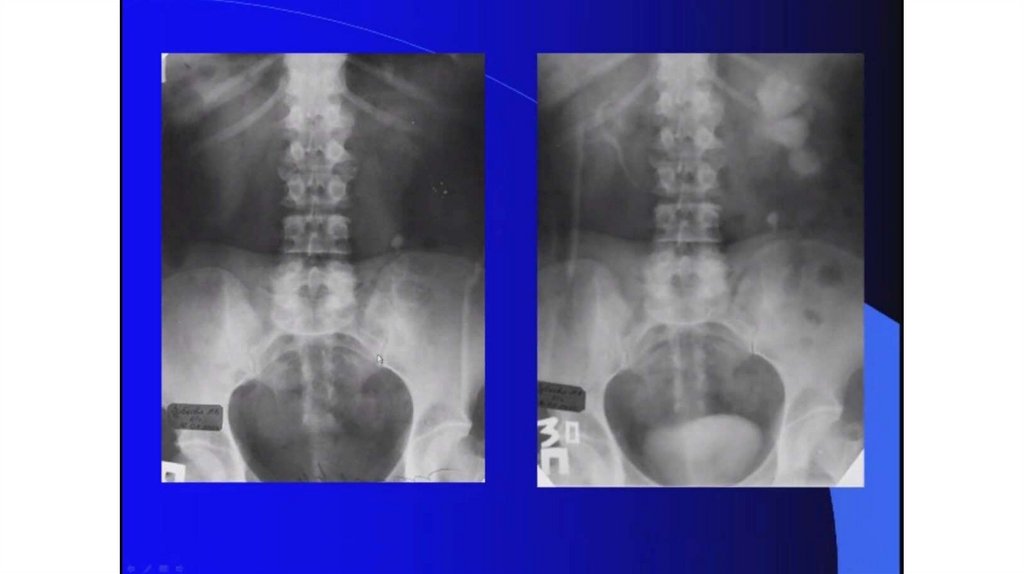

Мочекаменная болезнь. Мочекаменная болезнь и беременность

Мочекаменная болезнь